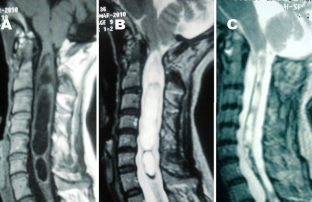

Sixteen adult patients with Chiari I malformation with significant ventral cervicomedullary compression, in the absence of BI, were included in the study. Atlantoaxial dislocation (AAD) was excluded in these patients by flexion-extension craniovertebral junction X-rays and computed tomography (CT). Their clinical profile, especially symptoms pertaining to cervicomedullary compression, i.e. dysphagia, dysarthria and spasticity, were graded. The ventral cervicomedullary compression (VCMC) was quantified using pBC2 (maximum perpendicular distance to the basion-infero posterior point of the C2 body) on sagittal magnetic resonance imaging (MRI) and only those patients with pBC2 ≥9 mm were included. Furthermore, retroversion of dens and retro odonotid tissue thickness was calculated in each patient. Fifteen patients underwent posterior decompression alone and one refused surgery. Follow-up was done every 3 months. Repeat MRI was done at 1 year following surgery to look for pBC2.

The mean pBC2 was 11 ± 0.2 mm. Retroversion of dens was responsible for VCMC in three patients and periodontoid crown in 13. There was no correlation between the tonsillar descent, age and the pBC2. All patients improved in symptoms of cervicomedullary compression following surgery. One patient worsened 6 months after initial improvement. The pBC2 did not change, as seen on follow-up MRI done in five patients.

VCMC in adult patients with Chiari I malformation in the absence of BI and/or AAD is due to periodontoid tissue (crown) or retroverted dens. Though a long-term study is required, it appears that all patients with Chiari I malformation, irrespective of the VCMC, can be given a chance with posterior decompression alone. Transoral decompression with posterior fusion may be required in a small subset of patients who fail to improve or worsen following posterior decompression only.